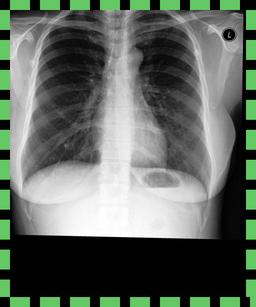

We found that many lateral acquisitions in the dataset were unexpectedly labelled as frontal (Figure 7(a)). Some images contained only noise (Figure 7(b)), non-human samples (Figures 7(d) and 7(e)) or incorrect anatomy (Figure 7(g)). Often, acquisitions with an incomplete field of view (FOV) (i.e., the lungs are not completely visible) were repeated (Figure 7(c)). Lastly, post-processed images were detected by the algorithm such as contrast-enhanced scans (Figure 7(i)) that are not often used for diagnostic purposes in clinical practice.

Curation of imaging datasets

CXR datasets [36] often contain multiple image acquisitions in a single visit due to data quality issues such as a limited field-of-view or scanning the wrong body part (Figure A.7). Unlike [9, 32, 81], we conduct curation to choose higher quality images among the potential candidates instead of performing a random selection. For this step, a separate BioViL-T is trained on ‘clean’ studies with single acquisitions and later used in a zero-shot setting to detect out-of-distribution samples [26, 27] arising from the re-imaging process. The candidate is selected as follows: for a margin . This approach is applied to enhance the quality of the temporal classification dataset given its limited size.